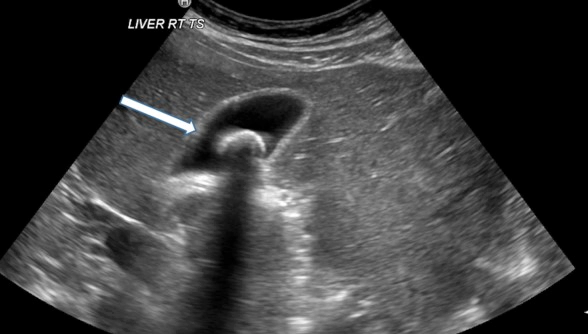

담적의 증상은 개인마다 다양하게 나타나기 때문에, 정확한 진단을 위해 의사의 상담이 필요합니다. 진단을 위해 초음파 검사, 혈액 검사, 자기 공명 영상(MRI) 등 다양한 검사가 진행될 수 있습니다. 증상이 발생하면 빠른 시일 내에 전문가와 상담하고 치료를 진행하는 것이 좋습니다.